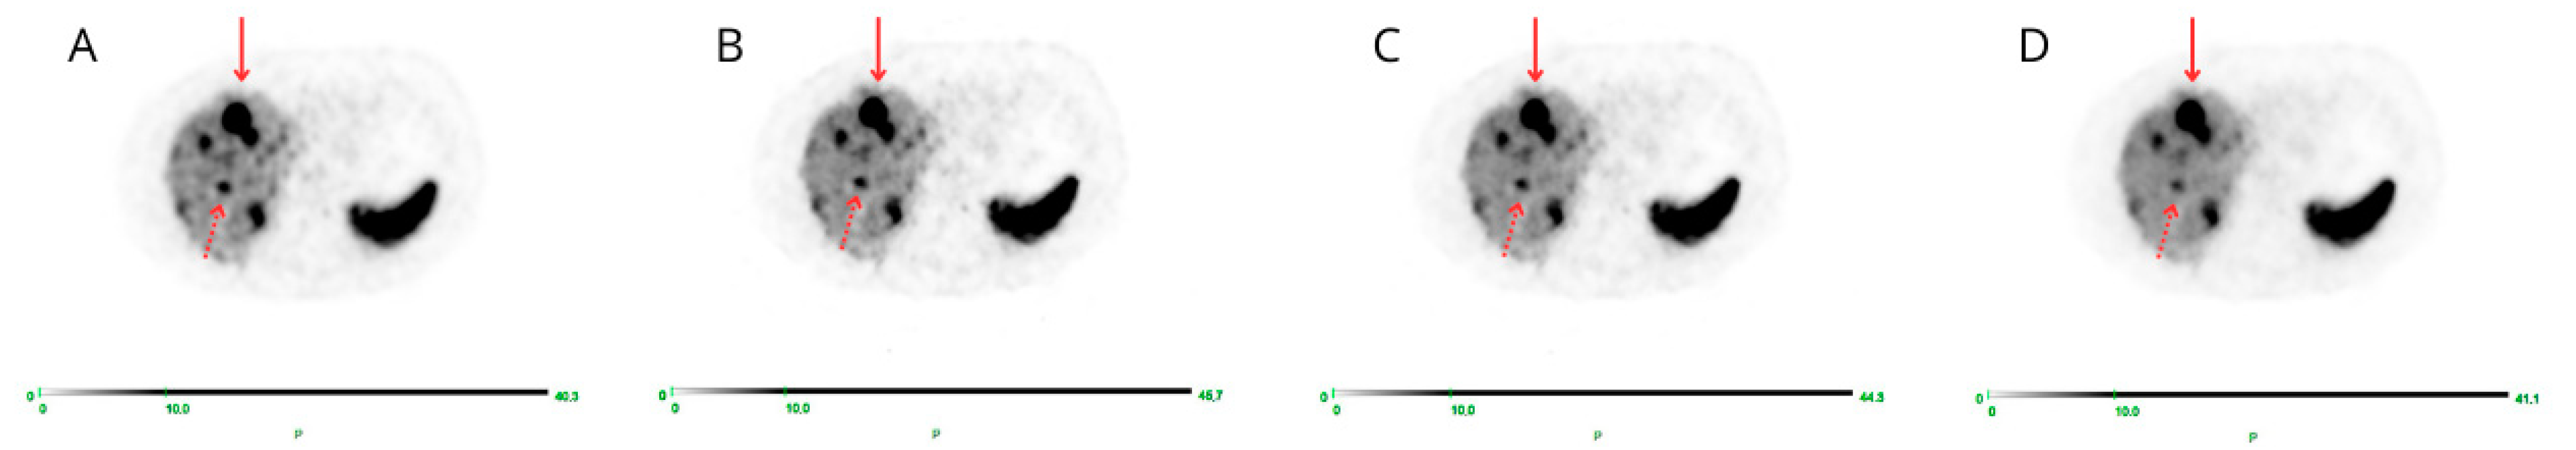

Visual image quality of PET β-1600 reconstruction was considered superior over the others (STD; β-800; β-1000) for both overall scan quality and single-lesion detection in all cases (52/52, 100%), with full agreement between the three readers (100%) (Figure 1 and Figure 2).

Figure 2.

Transaxial PET images corresponding to STD (A), β-level 800 (B), β-level 1000 (C), and β-level 1600 (D) are displayed: both T (red arrow) and t (dashed arrow) are better appreciated on the D image corresponding to β-level 1600.